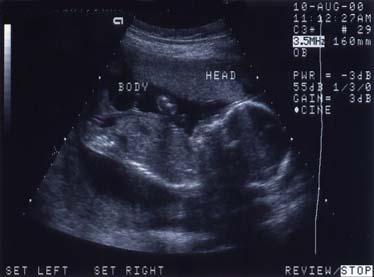

8/10/2000